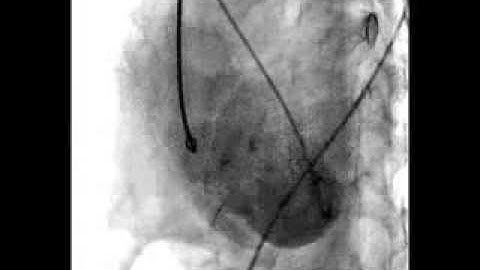

DrRaviRT- Large Post Myocardial Infarction Apical VSD transcatheter device closure